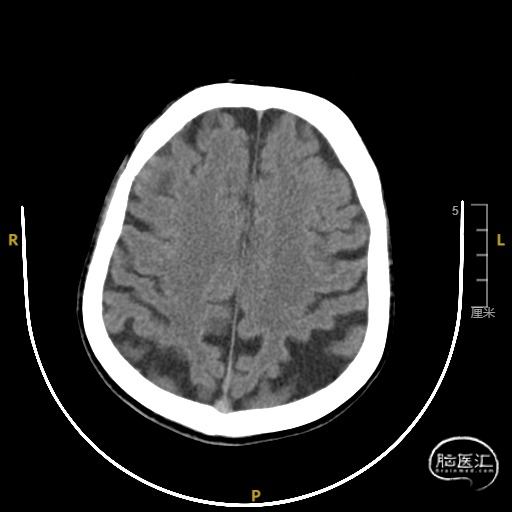

➢ 门诊头CT检查